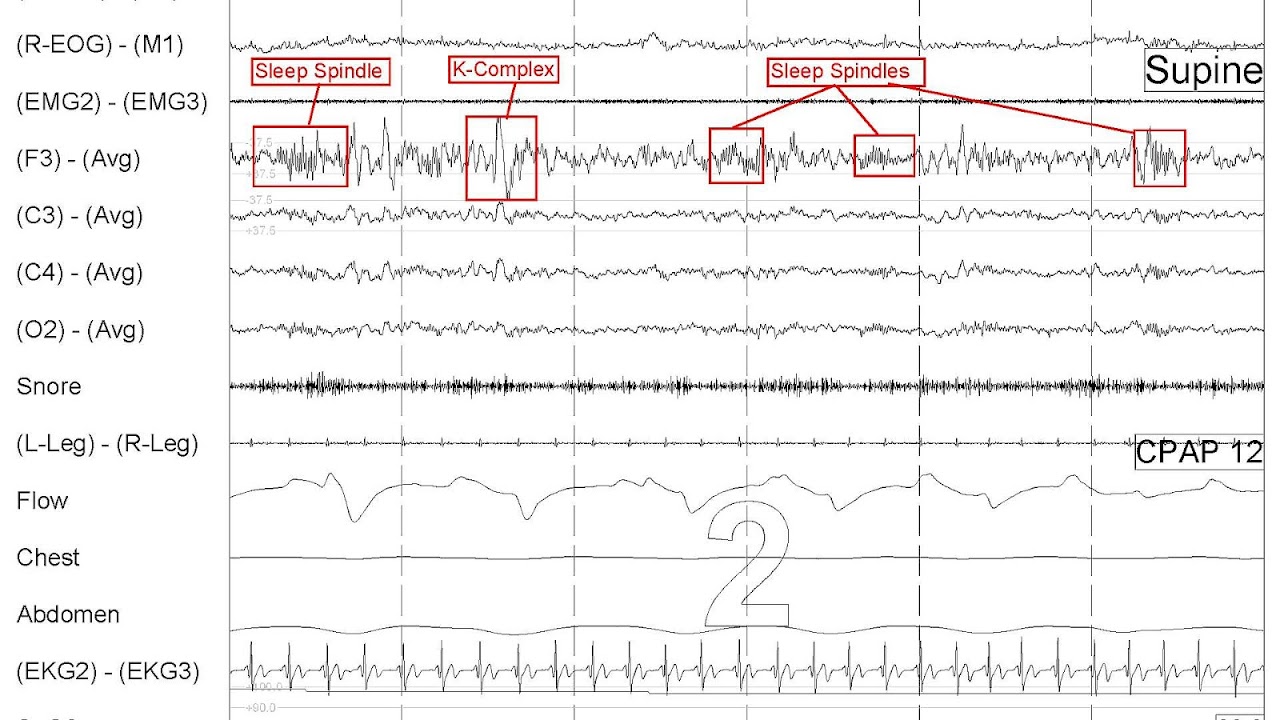

Sleep Spindles And K-Complexes Are Most Characteristic Of Which Sleep Stage . Stage ii is the predominant sleep stage during a normal night's sleep. Sleep spindles and k complexes are brief bursts of activity visible on electroencephalogram, or eeg, during n2 sleep. The distinct and principal eeg criterion to establish stage ii sleep is the appearance of sleep spindles. Sleep spindles and k complexes are unique to. Nrem stage 3 sleep is often. Sleep spindles are brief, powerful bursts of neuronal firing in the superior temporal gyri, anterior.

Sleep spindles are brief, powerful bursts of neuronal firing in the superior temporal gyri, anterior. Sleep spindles and k complexes are brief bursts of activity visible on electroencephalogram, or eeg, during n2 sleep. Nrem stage 3 sleep is often. Stage ii is the predominant sleep stage during a normal night's sleep. Sleep spindles and k complexes are unique to. The distinct and principal eeg criterion to establish stage ii sleep is the appearance of sleep spindles.

Sleep Spindles And K-Complexes Are Most Characteristic Of Which Sleep Stage Sleep spindles are brief, powerful bursts of neuronal firing in the superior temporal gyri, anterior. Sleep spindles are brief, powerful bursts of neuronal firing in the superior temporal gyri, anterior. Stage ii is the predominant sleep stage during a normal night's sleep. Nrem stage 3 sleep is often. Sleep spindles and k complexes are brief bursts of activity visible on electroencephalogram, or eeg, during n2 sleep. The distinct and principal eeg criterion to establish stage ii sleep is the appearance of sleep spindles. Sleep spindles and k complexes are unique to.